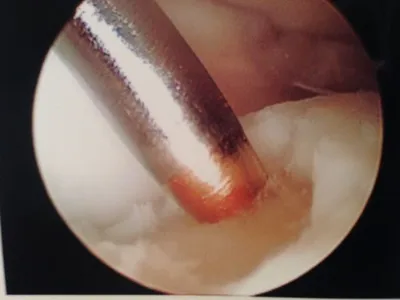

Action shot of microfracture of talus OCD.

Bleeding of OCD after microfracture.